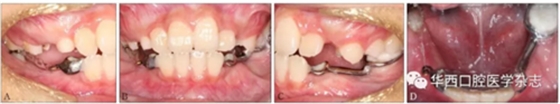

經(jīng)過綜合分析及考慮患者的意愿,制定開窗-正畸協(xié)同治療方案,術(shù)前拔除尚未萌出的45牙為牽引46牙提供間隙,通過鑄造板將36、73、32、31、42、41、83牙連接成一整體,為牽引46牙提供支抗(圖4)。

A:右側(cè)像;B:正面像;C:左側(cè)像;D:下頜面像。

圖 4 矯治器初裝口內(nèi)像

46牙開窗并將舌側(cè)扣粘接于近中面。用玻璃離子將鑄造板粘接在下頜,橡皮鏈通過83牙遠中的牽引鉤和46牙上的舌側(cè)扣相連,橡皮鏈牽引時對46牙產(chǎn)生一個順時針旋轉(zhuǎn)的作用力。術(shù)中牽引1個月時,見46牙產(chǎn)生順時針旋轉(zhuǎn)(圖5、6)。治療5個月時,46牙產(chǎn)生明顯的順時針旋轉(zhuǎn),基本直立(圖7),由于此時下頜雙側(cè)乳尖牙脫落,下頜鑄造板無法固位,于是拆除矯治器,觀察隨診,待后期其余牙齒萌出后行全口固定正畸矯治。